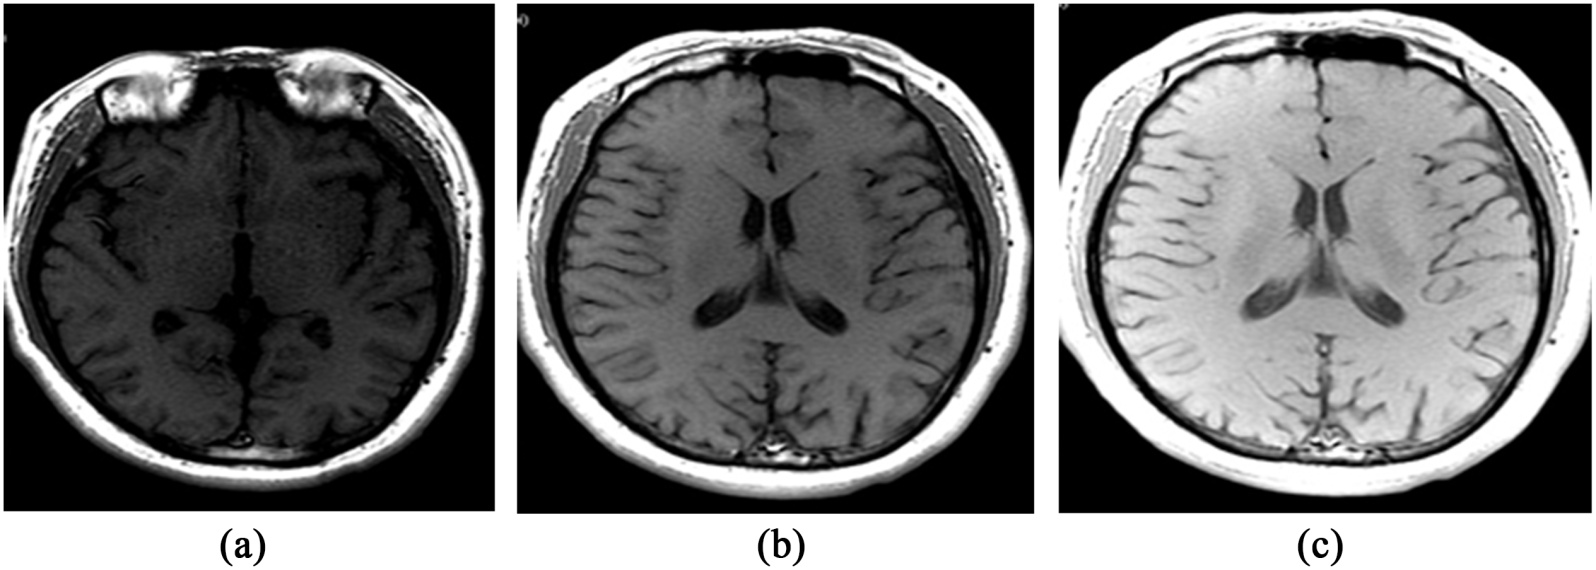

(2) 案例分析:中期通过CBL进行案例讨论,案例选取平时工作中的常见病,以解剖、临床、影像技术及影像诊断的基础知识为依据,培养学生举一反三联合思维的能力,增强学生的临床推理能力(图2)。

Figure 2. Comparison of MRI images acquired with different imaging parameters

2. MRI不同成像参数扫描图像对比

图2(a)~(c)均为头颅磁共振T1加权成像(T1-weighted imaging),但图像清晰度存在明显差异。其根本原因在于重复时间(repetition time, TR)的不同:TR越长,纵向磁化恢复越充分,信噪比(signal-to-noise ratio, SNR)越高,因此图2(c)的图像比图2(a)更清晰。本案例可引导学生在PBL环节中自主探讨TR对成像质量的影响,并在教师解答与总结后,深刻理解正确选择磁共振参数对获取高质量影像的重要性,从而激发学习主动性并培养独立思考能力。